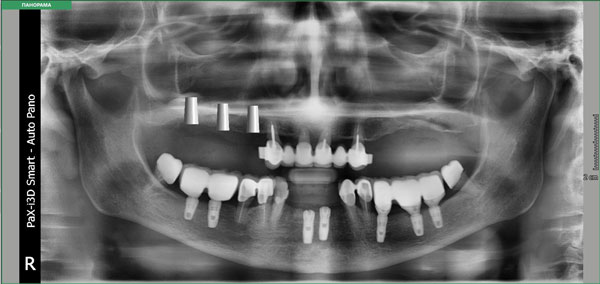

Также при планировании имплантации после операции синус-лифтинг, хирург зачастую сталкивается с необходимостью получать четкие данные о плотности аутотрансплантата или остеопластического материала с целью подготовки к следующему оперативному этапу. В таких случаях 3D-технологии помогают произвести волюмометрическую оценку синус-лифтинга в отдаленные сроки. Применить специальный планировщик дентальной имплантации в программном обеспечении Ez3D-i. При виртуальной установке имплантата посредством различных инструментов, возможно правильно наметить оси, измерить ширину альвеолярного отростка, расстояния от вершины альвеолярного гребня до дна верхнечелюстных пазух. С помощью специально встроенной опции производится выбор системы - производителя дентальных имплантатов, длины и диаметра имплантата, цветовые показатели мультимедийного ролика. После того как программа спозиционировала имплантат, хирург может моделировать его ангуляцию, инклинацию и погружение, учитывая все анатомические факторы риска. Также существуют функции "Удалить или Скрыть" имплантат, тогда возможно настроить по-другому планировщик и выбрать имплантат другой длины и диаметра или иной марки производителя (Рис.2).

Рис.2 Дентальная объемная томограмма и ортопантомограмма. Планировщик программного обеспечения Ez3D-i и EzDent-i. Виртуальная инсталляция дентальных имплантатов в проекции отсутствующих 15,16,17 зубов после аугментации альвеолярного отростка посредством операции открытый синус-лифтинг